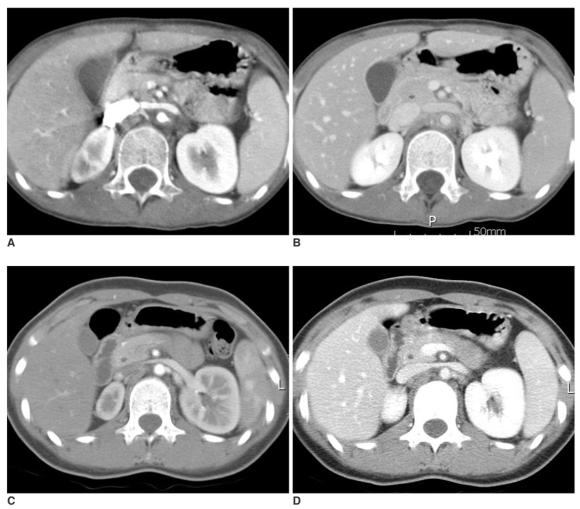

The initial CT findings included high density and calcifications of the aortic wall in the precontrast images and a thickened wall with enhancements in the arterial and the venous phases. A low-attenuation ring was demonstrated in the venous phase in 15 patients (83%). On the follow-up evaluation, the mean mural thickness decreased significantly from 4.1 mm to 2.4 mm. The mean mural attenuation ratio in the venous phase decreased significantly from 1.9 to 1.3 (p = 0.001). The low attenuation ring was identified in seven patients (39%) who had only with active, persistent Takayasu arteritis.

初始CT表现包括平扫图像上主动脉壁高密度及钙化,动脉期和静脉期壁增厚且强化。15例患者(83%)在静脉期显示低密度环。随访评估时,平均血管壁厚度从4.1mm显著降至2.4mm。静脉期平均血管壁衰减比值从1.9显著降至1.3(p = 0.001)。仅在13例活动期、持续性大动脉炎患者中的7例(39%)发现低密度环。